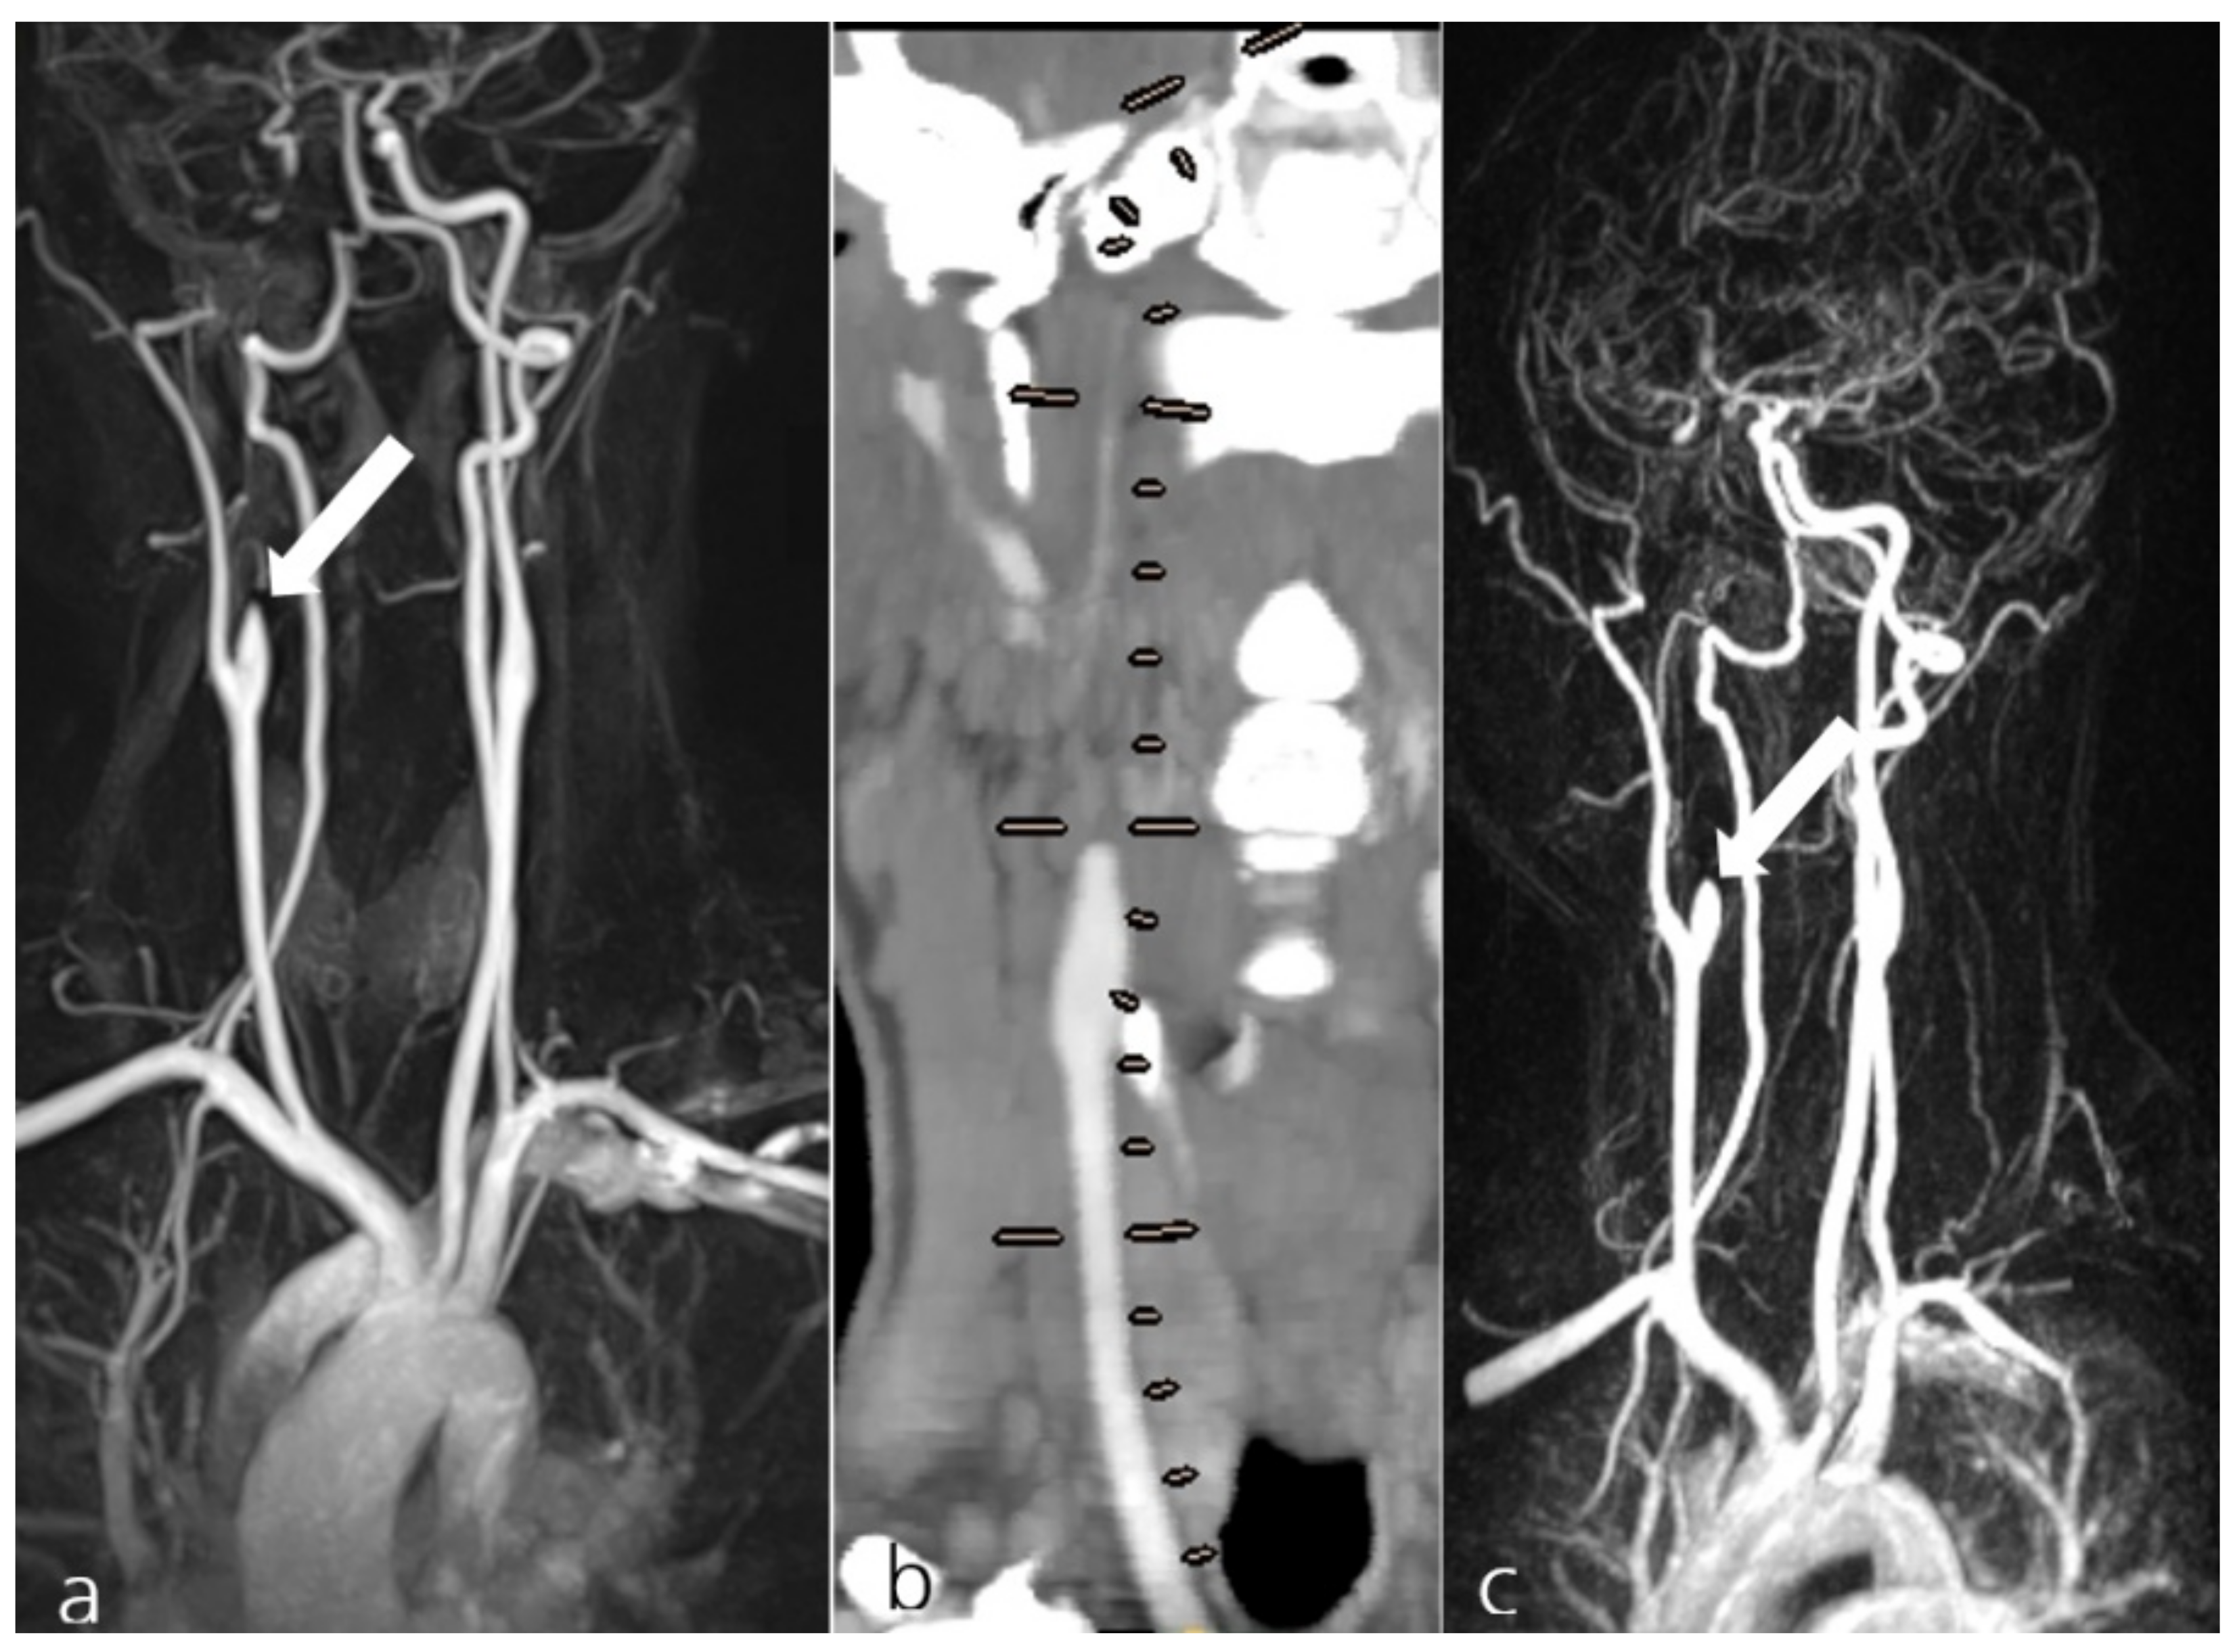

Figure 1. Exemplary display of patient #39 from group I, presenting with a spontaneous dissection of the right internal carotid artery (a, arrow). The MRA shows the collateral supply for the occluded artery. The patient received 100 mg ASA and 90 mg Prasugrel PO daily. Follow-up examinations at 4 years (CTA, b; lines show presumed course of the occluded right ICA) and at 4.5 years (c) showed the persistent occlusion of the dissected artery while still under AT treatment (c, arrow).